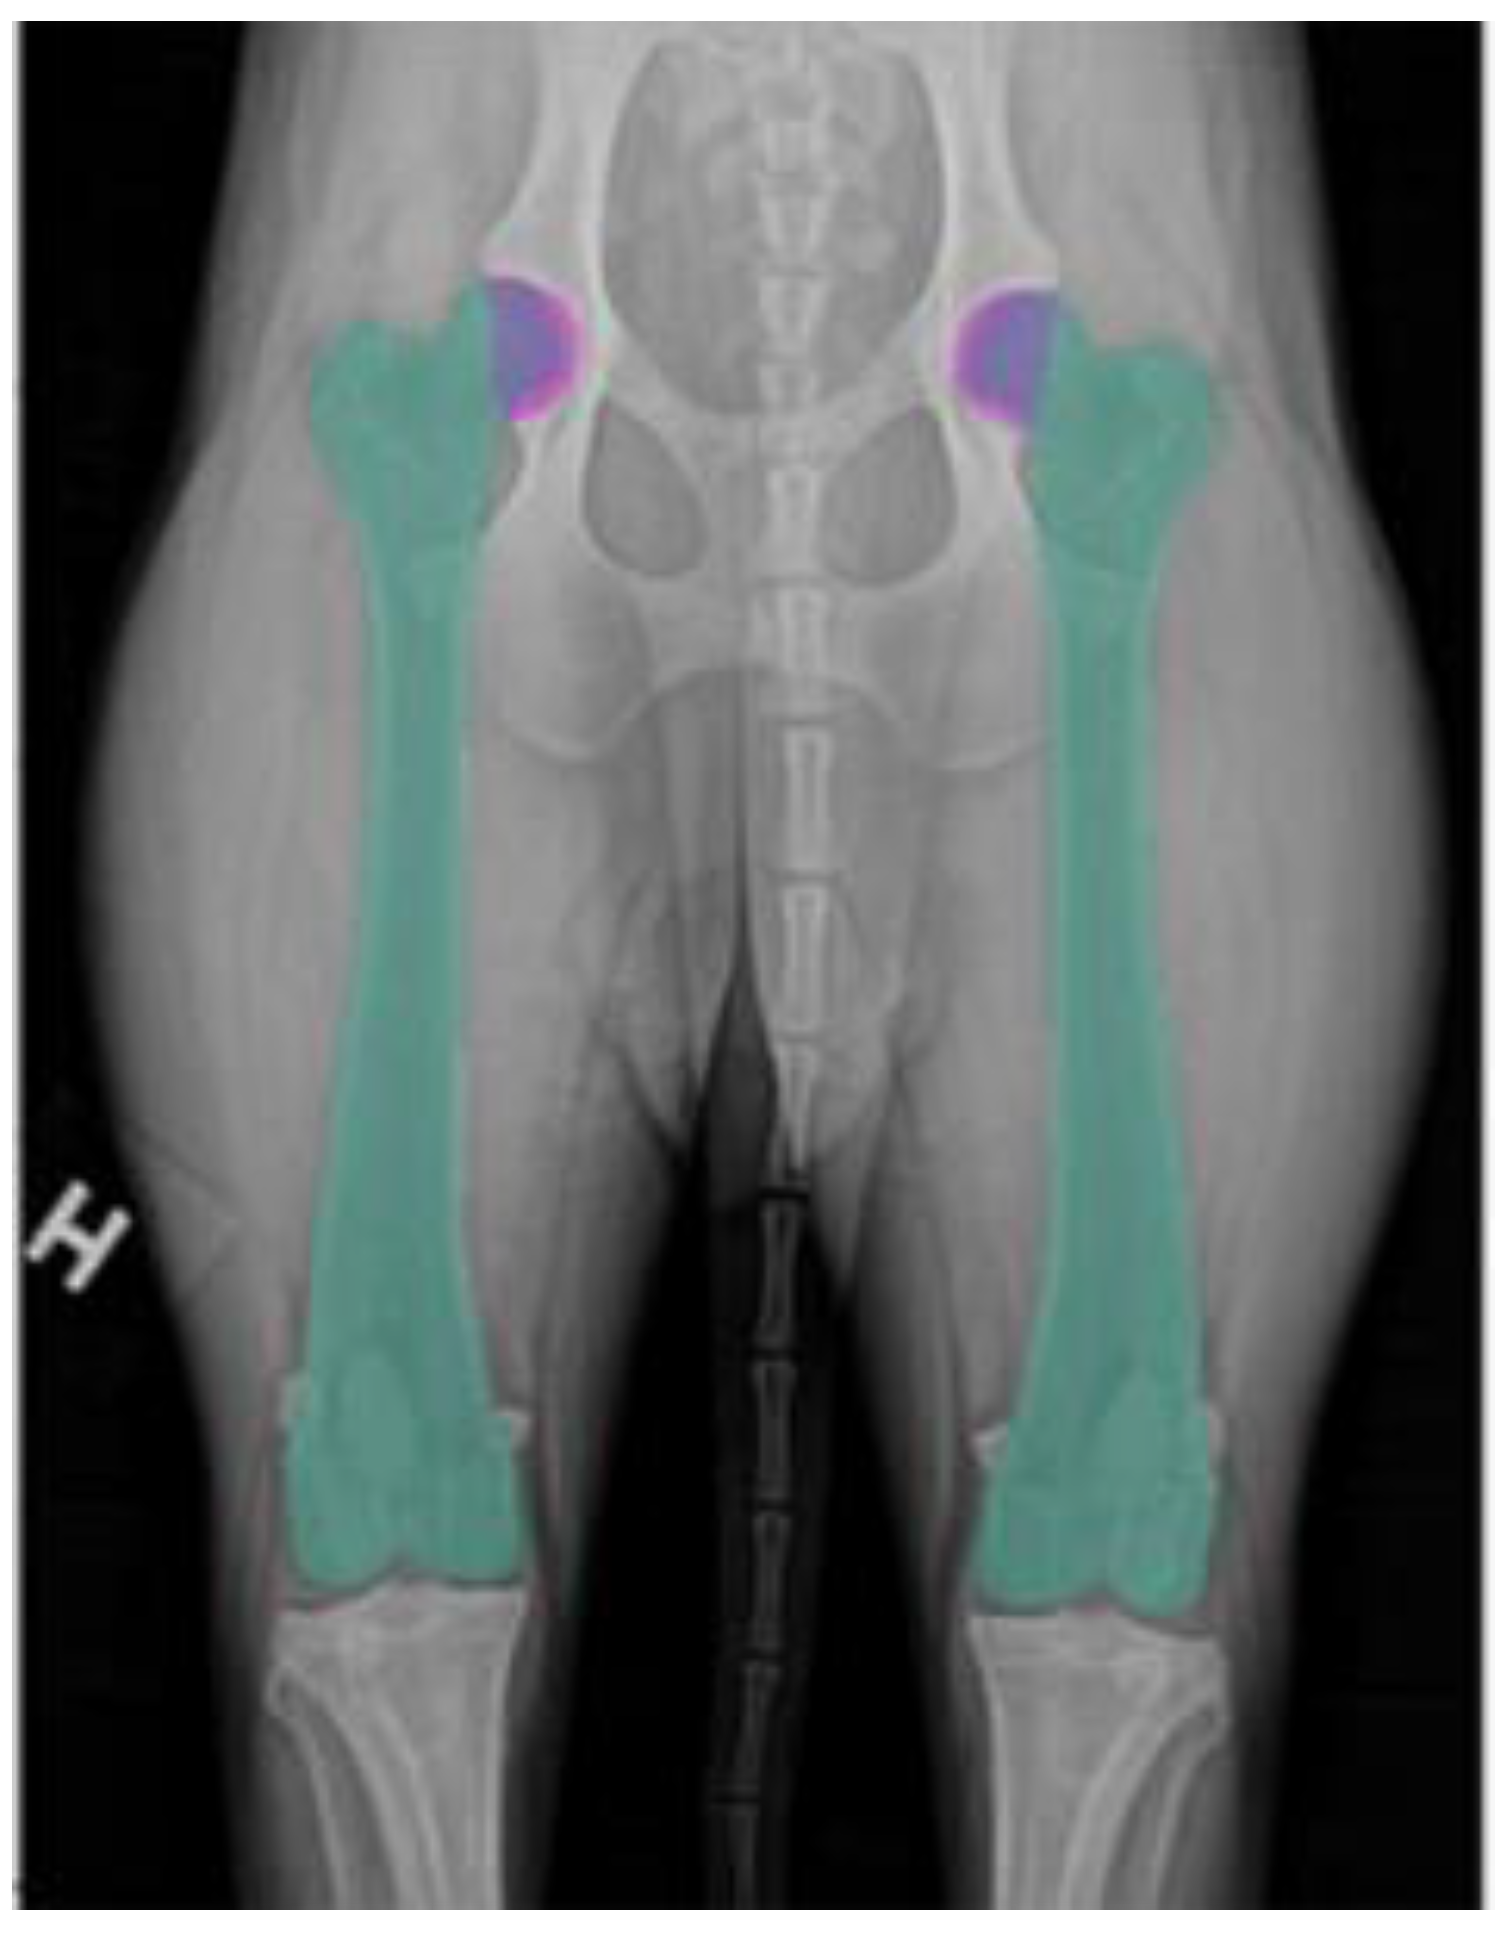

To prepare the dataset for training, each VDHE image was manually segmented using the LabelMe polygonal image annotation tool [25]. P.F.-G. carefully delineated and labeled the femur and acetabulum in both hip joints, ensuring accurate and well-defined anatomical boundaries (Figure 4).

Figure 4. Anatomical annotations of the femur and acetabulum. The green regions correspond to the femur, the pink regions represent the acetabulum, and the blue areas indicate the overlapping regions between the femoral head and the acetabulum.